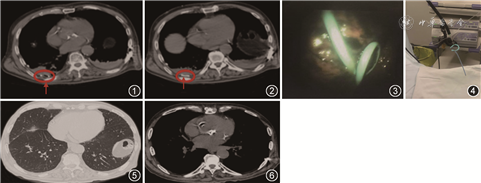

患者男,69岁,因“发作性胸痛20余年,加重7 h”于2018年11月26日入院。初步诊断:(1)冠状动脉粥样硬化性心脏病,急性冠脉综合征,急性左心力衰竭;(2)心脏瓣膜病,主动脉瓣关闭不全;(3)高血压2级;(4)2型糖尿病。2018年11月28日行床旁胸腔彩超:双侧胸腔积液(右侧范围约4.1 cm×8.2 cm,左侧范围约4.5 cm×9.0 cm),于2018年11月30日在超声引导下行右侧胸腔置管引流术。2018年12月2日护理人员发现胸腔引流管离断,引流管头端部分留置体内,急诊行胸部CT证实引流管残端位于右侧胸腔内(图1,2)。2018年12月3日请呼吸内科、心内科、胸外科、超声科、麻醉科等相关科室会诊,建议行内科胸腔镜异物取出术。停用抗血小板药物5 d后,患者于2018年12月12日在局部麻醉下行内科胸腔镜检查。操作过程:使用日本OLYMPUS公司LTF-240型半硬质电子内科胸腔镜,患者左侧卧位,消毒、铺巾后,选右侧腋中线第6肋间,2%利多卡因局部麻醉后,顺肋间隙切开皮肤约1.5 cm,钝性分离皮下及肌肉组织,至胸膜突破后置入戳卡,送入胸腔镜,可见引流管(图3),应用异物钳取出(图4),镜下诊断:胸腔内异物。操作过程顺利,术中及术后无特殊不适。术后当日及次日复查胸片未见胸腔内异物,余无明显异常。2018年12月19日复查胸部CT:双肺散在慢性炎症/纤维灶,双侧胸腔积液较前(2018年12月2日)均有减少,未见胸腔内异物及胸腔积液(图5,6)。